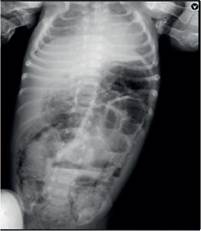

Las primeras 24 horas se mantuvo con de medio interno y vía oral; se inició cobertura antibiótica por persistencia de vómitos2 y diarreas acuosas10, con Ampicilina (200mg/kg/ día) + Cefotaxima (50mg/kg/día) por los 4 días siguientes, durante ese periodo se observó incremento del flujo de deposiciones hasta 11.8 cc/kg/h con necesidad de reposición hídrica; al 5to día presentó distensión abdominal marcada con residuo gástrico bilioso y deterioro hemodinámico, se realiza una radiografía abdominal evidenciando distensión de asas intestinales y neumatosis difusa (Fig N°1.). Es así que ingresa a sala de operaciones y se observa la presencia de líquido claro escaso, neumatosis intestinal - parietal y palidez difusa yeyuno-ileal; realizándose la ileostomía, 12cm de la válvula íleo cecal a doble boca.

Figura 1: Radiografía abdominal con distención de asas y neumatosis difusa, asociado a niveles hidroaéreos